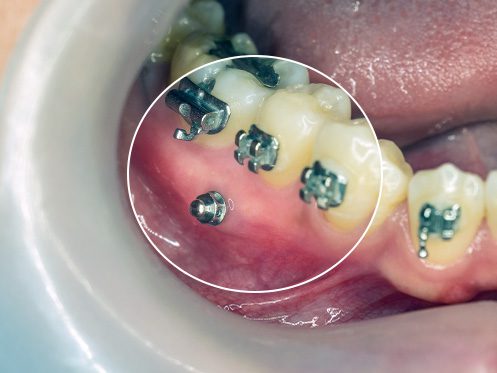

Mini Implantes Ortodónticos También llamados microtornillos o microimplantes, son pequeños anclajes de titanio que se colocan temporalmente en el hueso maxilar o mandibular para facilitar y controlar mejor el movimiento de los dientes durante un tratamiento de ortodoncia. A diferencia...